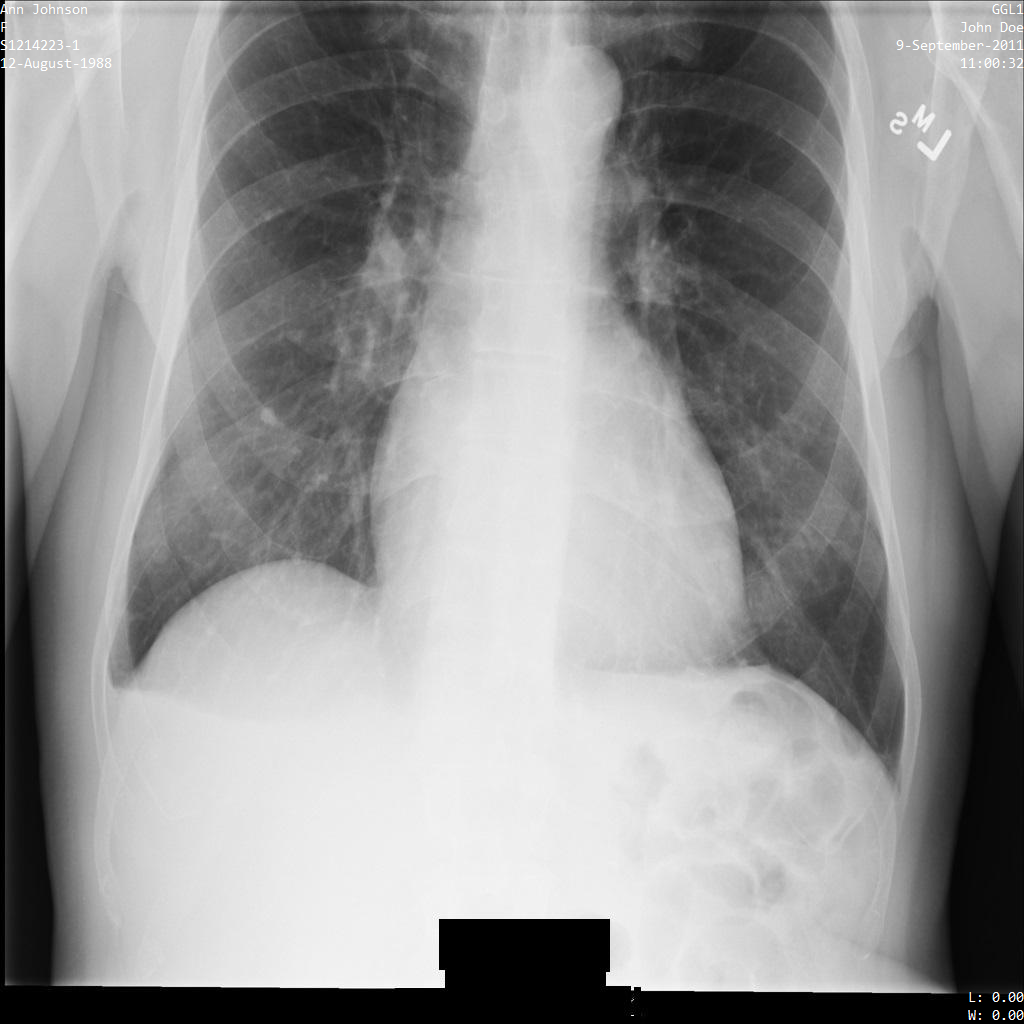

L'image suivante montre une radiographie non masquée d'un patient :

Une fois l'image envoyée à l'API Cloud Healthcare à l'aide de l'option REDACT_SENSITIVE_TEXT, elle apparaît comme suit :

Vous pouvez constater que les événements suivants se sont produits :

- Le paramètre

PERSON_NAMEen bas à gauche de l'image a été masqué. - Le paramètre

DATEen bas à gauche de l'image a été masqué.

Le sexe du patient n'a pas été masqué, car il n'est pas considéré comme du texte sensible selon le paramètre infoTypes DICOM par défaut.